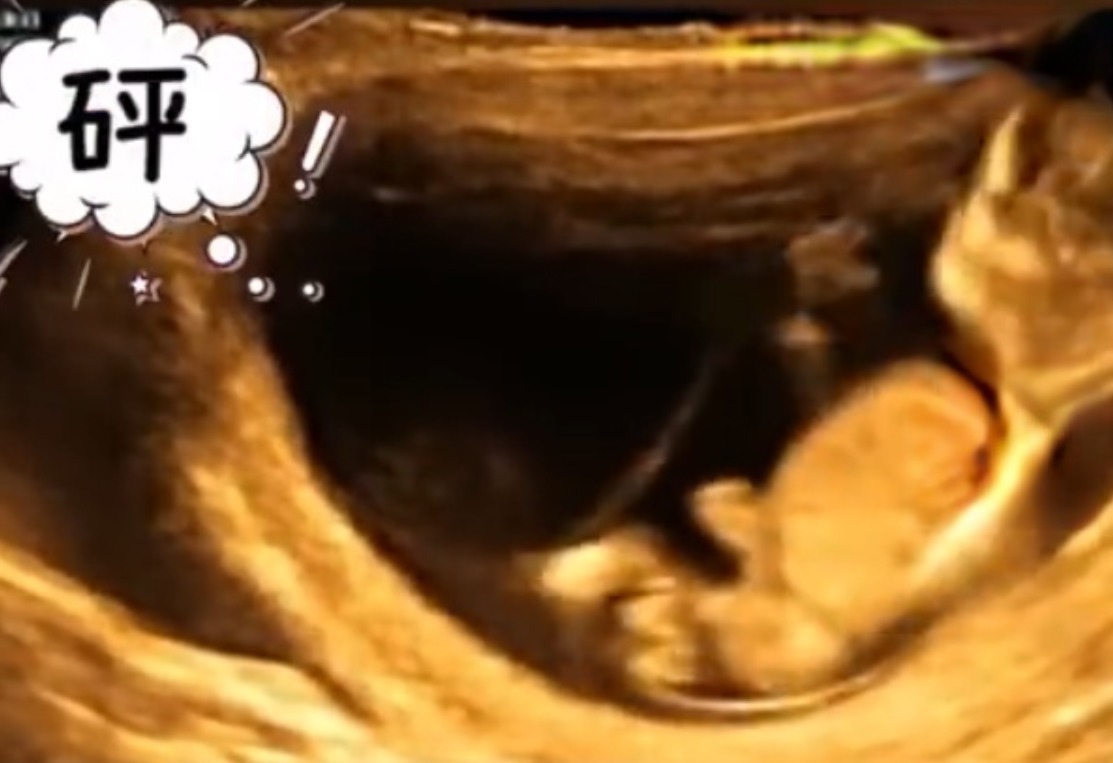

可能孩子在妈妈肚子里在汲取营养或是吮吸手指,这是常见的现象。但生活中也有十分罕见的,在河南有一位孕妈做四维彩超的时候突然开始腹痛,能感受到宝宝在肚子里的活动。做B超的时候发现两个宝宝正在闹着玩,在妈妈的肚子里打架。看到了这两个宝宝的未来一定是一个挨揍一个受欺负。网友们纷纷震惊评论说“看起来是单方面的在挨打。”“所以我下个月预产期,等他长大了我就找机会揍他一顿,不然不能泄愤。”“抢位置大作战。”